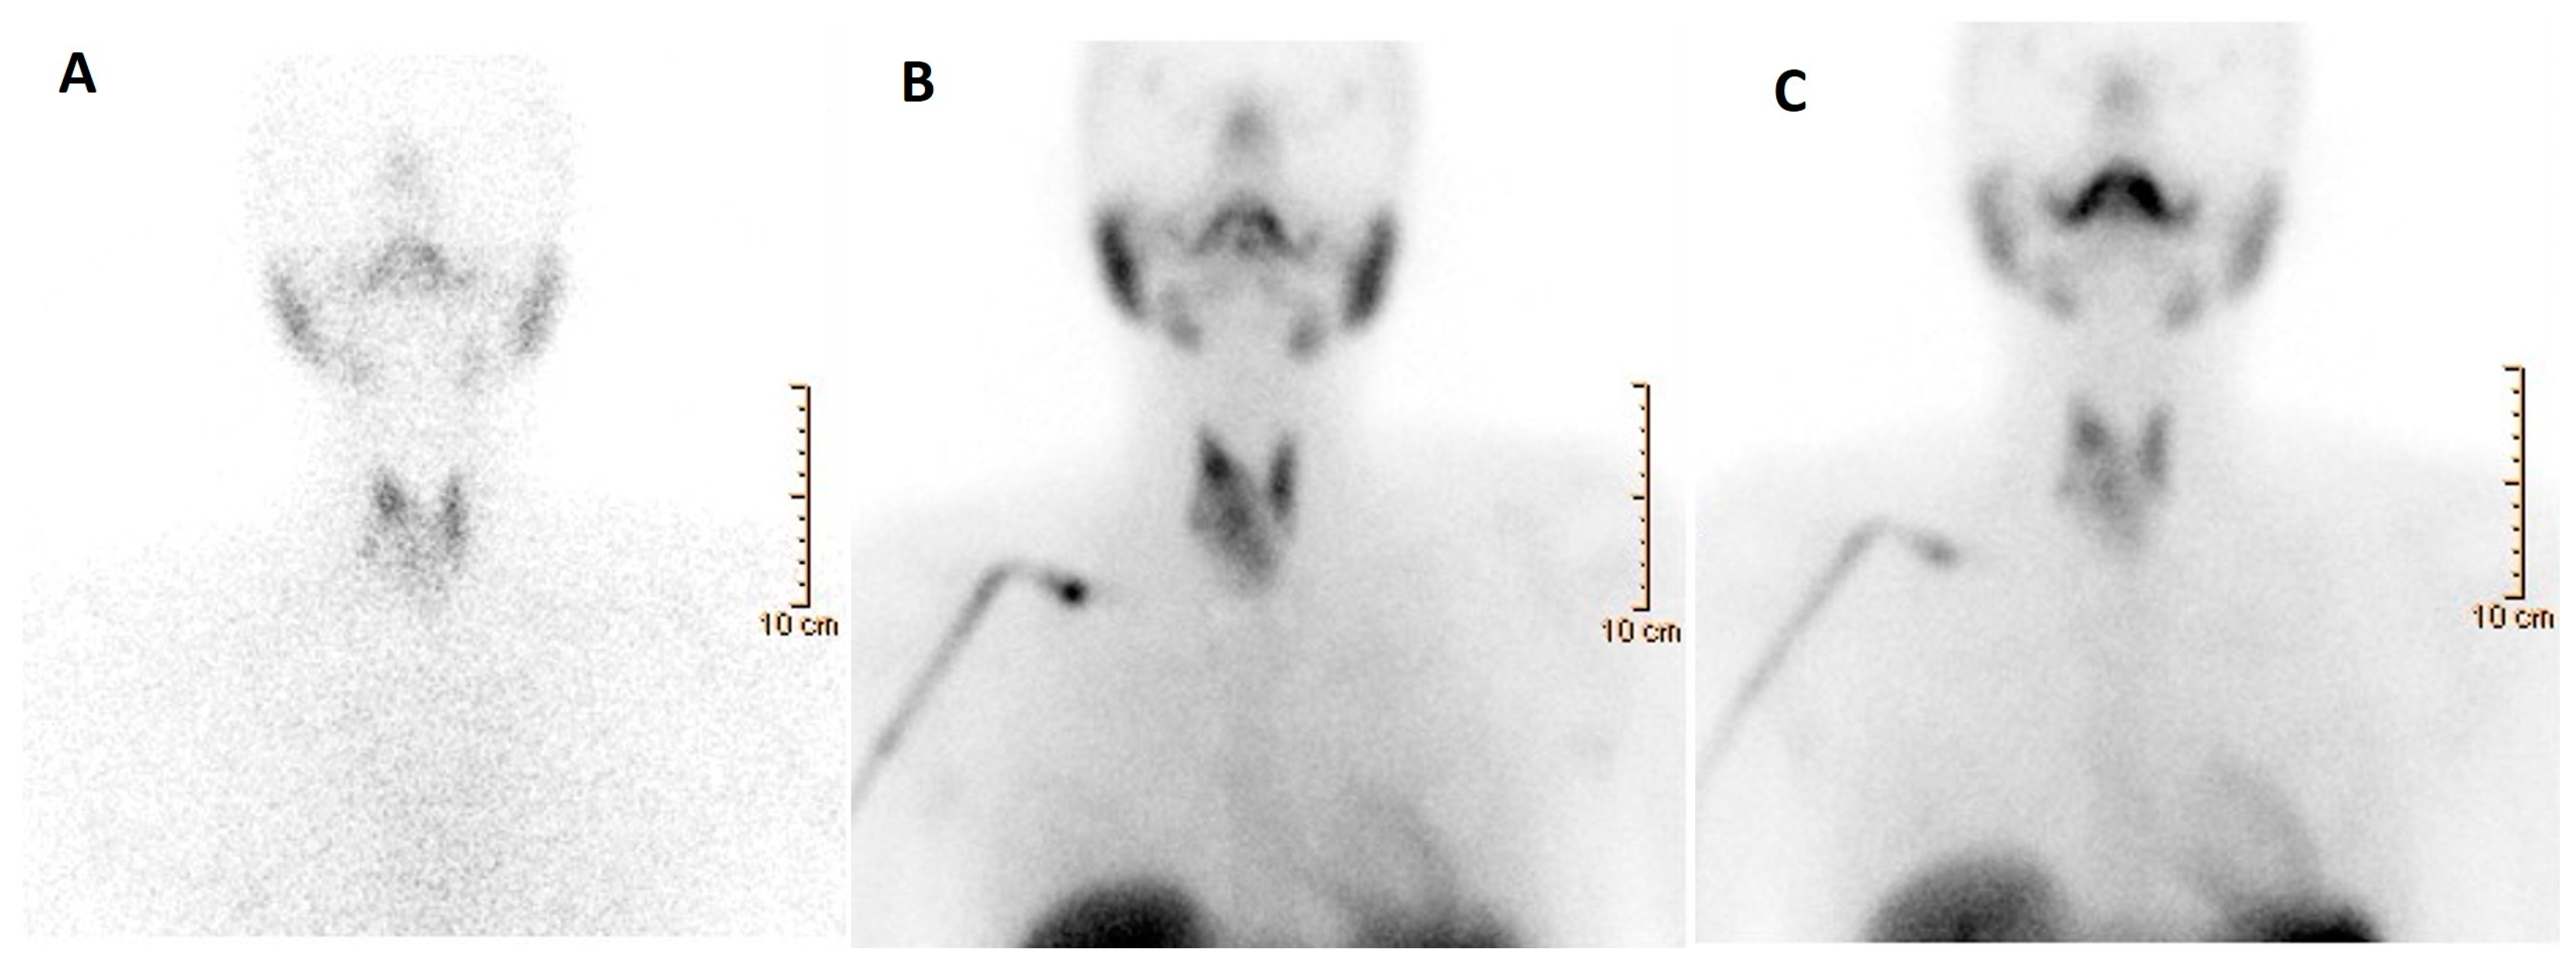

- Giovanella, L.; Avram, A.M.; Iakovou, I.; Kwak, J.; Lawson, S.A.; Lulaj, E.; Luster, M.; Piccardo, A.; Schmidt, M.; Tulchinsky, M.; et al. EANM Practice Guideline/SNMMI Procedure Standard for RAIU and Thyroid Scintigraphy. Eur. J. Nucl. Med. Mol. Imaging 2019, 46, 2514–2525. [Google Scholar] [CrossRef]

- Giovanella, L.; Ceriani, L.; Treglia, G. Role of Isotope Scan, Including Positron Emission Tomography/Computed Tomography, in Nodular Goitre. Best Pract. Res. Clin. Endocrinol. Metab. 2014, 28, 507–518. [Google Scholar] [CrossRef] [PubMed]